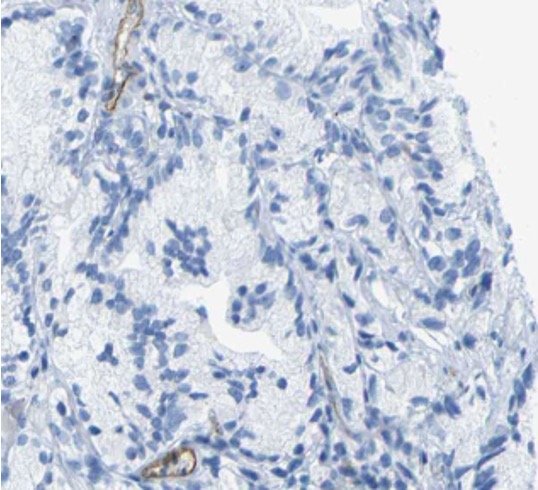

Immunohistochemistry images from the Human Protein Atlas were evaluated as well. The sample with CD93 being stained showed no expression of CD93 protein, which suggests a translational issue with CD93 in prostate cancer. The CD93 mRNA is present, but the protein is not. The image to the right shows a lack of CD93 protein expression.